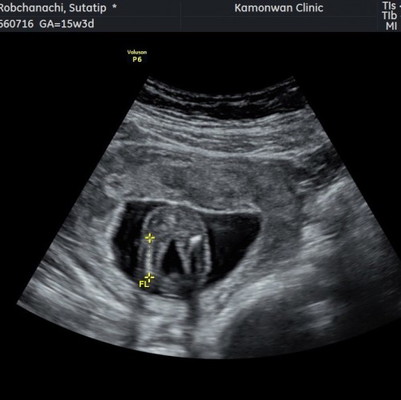

15w4d น้องนอนคว่ำ แต่ป้าหมอให้ดูทางก้นคาดว่าจะเป็นผู้หญิง แม่ๆบ้านอื่นน้องให้เห็นเพศยังคะ

บ้านนี้17+2 คุณหมอให้ทางไปผู้หญิง แต่ไม่100%คะ

ช่วยดูให้หน่อยค่ะแต่แม่ไม่เห้นกลีบเลย🤣

16+2w น่าจะ ผญ เหมือนกันคะ